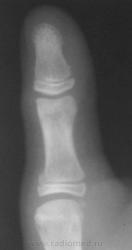

Рентгенография 1-го пальца. Девочка 11 лет.Травма.

Остеоэпифизеолиз о/ф первого пальца.

А что смущает? вроде обычный остеоэпифезиолиз проксимального эпифиза дистальной фаланги 1пальца   кисти.